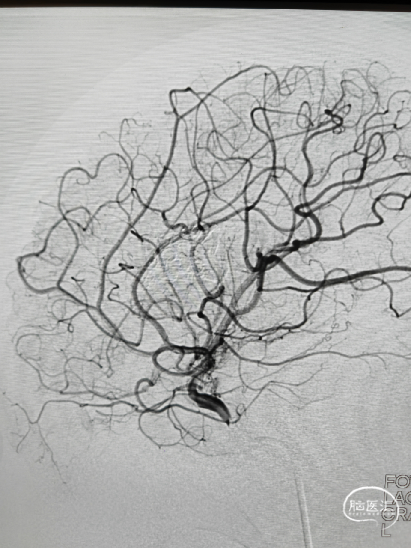

男,27岁,中度昏迷,AVM破裂出血破入脑室

双豆纹动脉加大脑中动脉分支供血,大脑大静脉引流,由于豆纹动脉与大脑中动脉成锐角,超选困难,采用球囊辅助echelon10才顺利进入豆纹动脉。

微导管自身block作用,无需做高压锅塞子,注胶过程几乎没有返流,Onyx胶很快完全弥散畸形团,闭塞引流静脉并倒灌其它供血动脉。

Onyx胶铸型完全,供血动脉、畸形团、引流静脉充分闭塞。术后正侧位及3D造影,畸形团及引流静脉完全不显影。